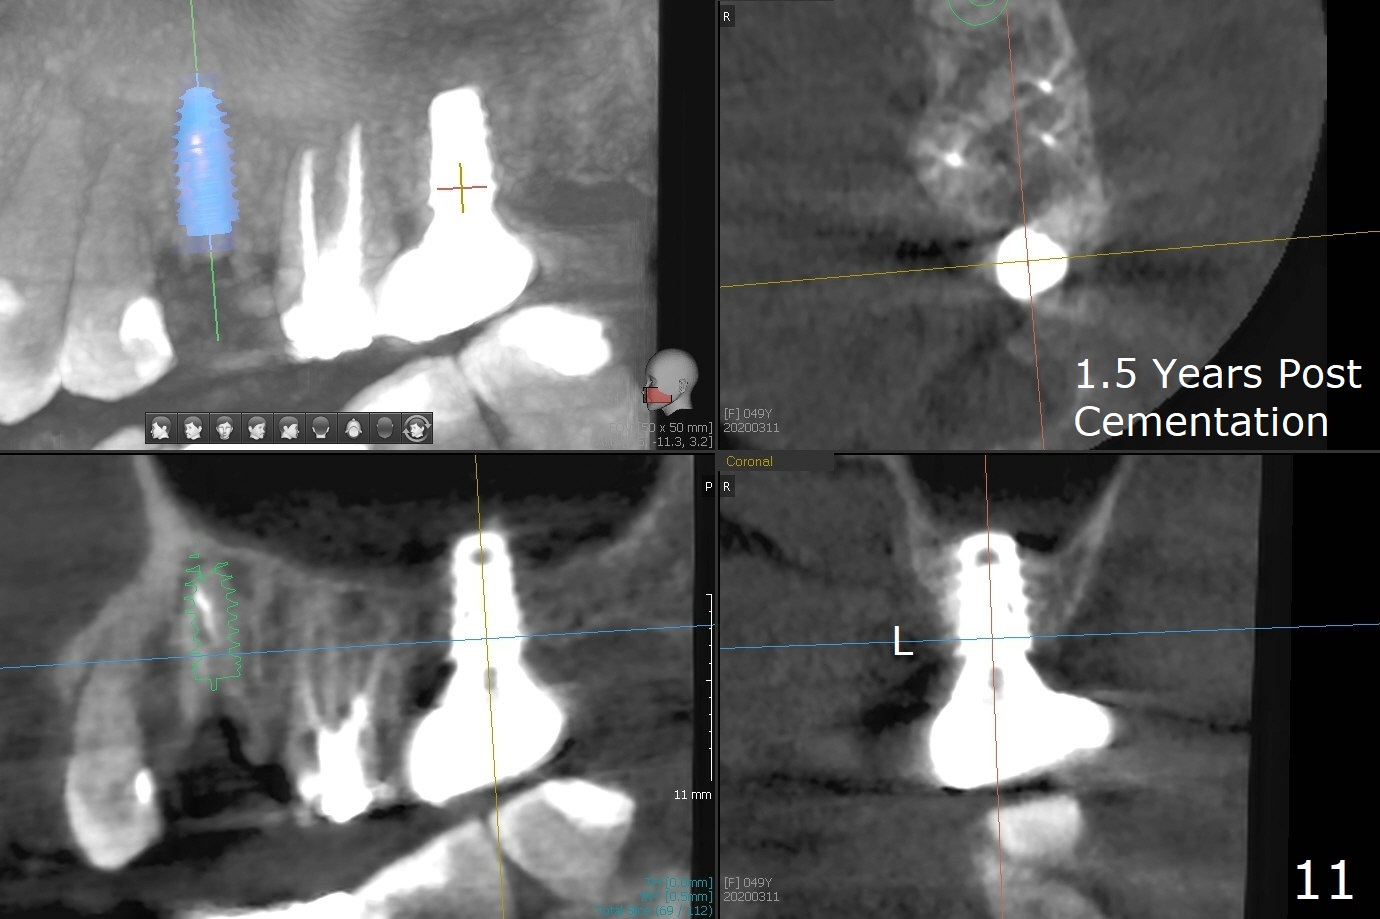

After removal of the mesial (M) and distal (D) residual roots of the tooth #15 (Fig.1,2), Magic Split is used to test bone density (high), followed by Magic Drills from Magic Sinus Lift Kit (for 4 mm) and Magic Surgical Kit (for 5 mm). It appears that the sinus floor has been perforated with the intact sinus membrane. Following minimal use of Magic Lifter, Vanilla Graft is inserted (Fig.3,4 *) and a 4x9 mm dummy implant is placed. After placement of more allograft (Fig.5 *), a 5x7 mm implant is placed with ~ 35 Ncm. With placement of a 5.5x4(2) mm abutment, an immediate provisional is fabricated to close the socket. Six months postop, the bone graft remains in the sinus around the apical end of the implant (Fig.6 *), while there seems no bone loss coronally (Fig.7). In fact there is, as shown later (Fig.8-11 < and lingual (L)). The crown is recemented 6 months post cementation (due to short abutment). The abutment seems to be incompletely seated. When the crown at #14 is reprep following #13 implant, the abutment screw is being untightened, the crown dislodges first. The abutment is confirmed short with more than enough occlusal clearance. After use of 5.5 and 6.0 mm bone profile drills, a 5x4(3) mm abutment is placed with complete seating.